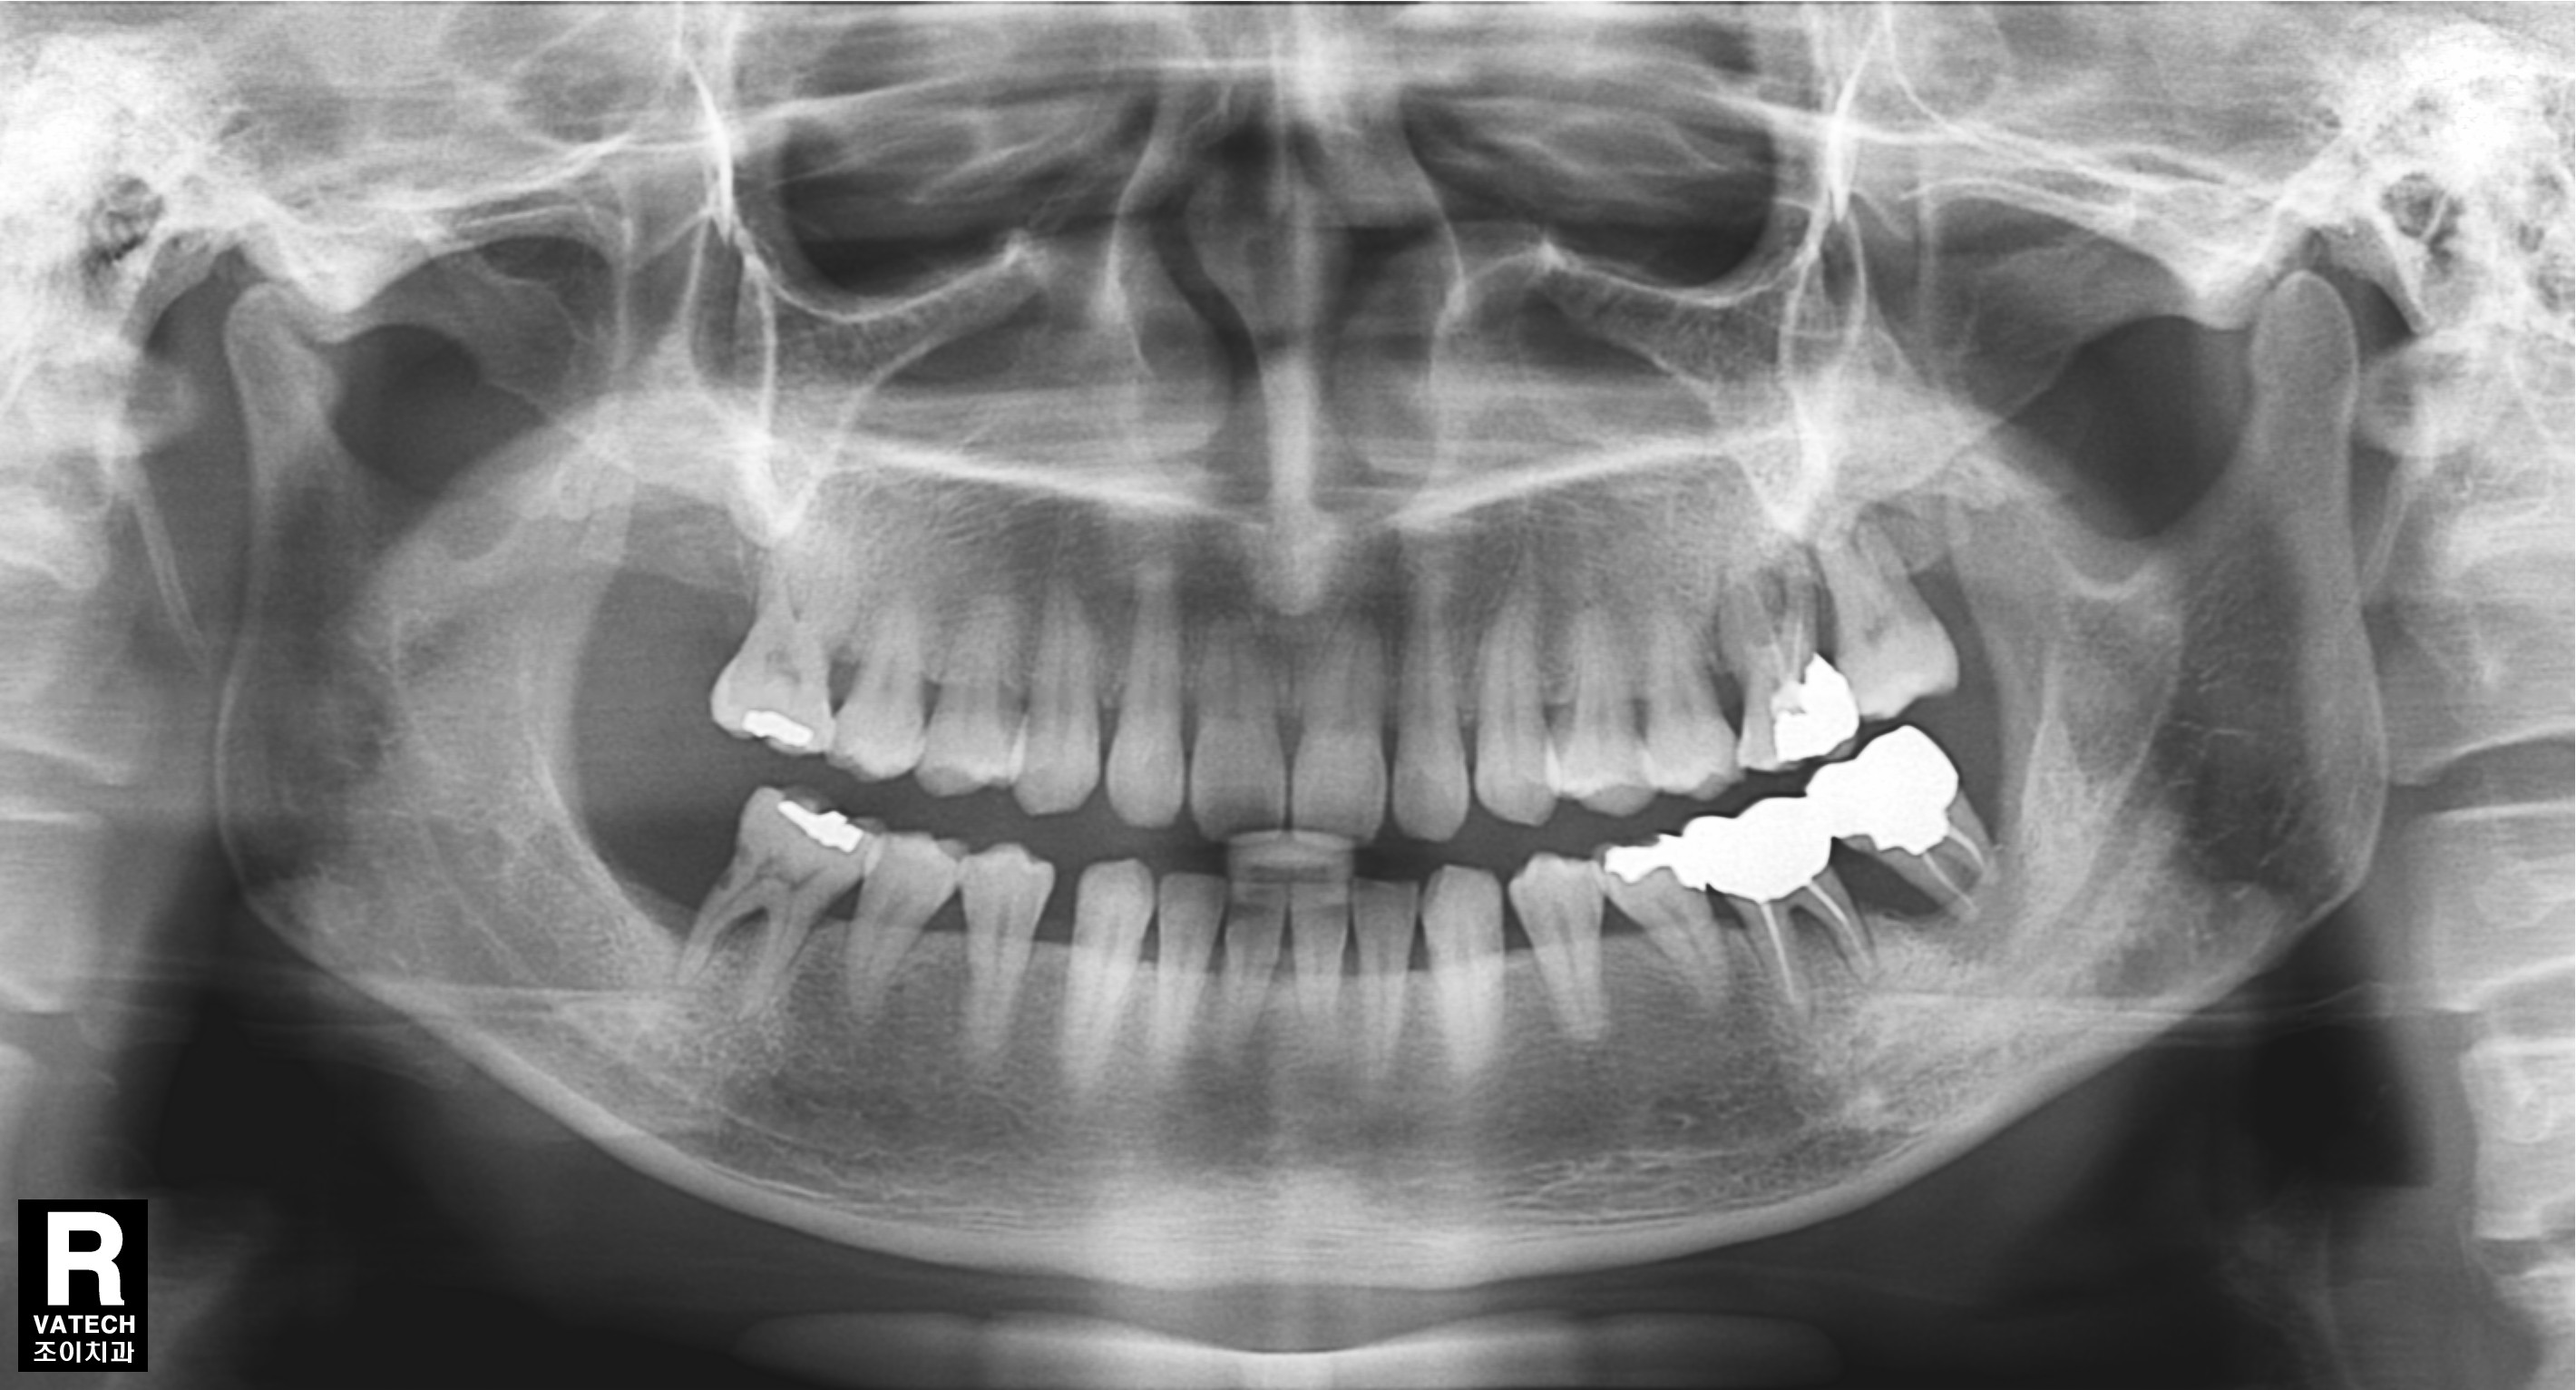

치주질환으로 치조골이 많이 녹아 내려간 경우 원하는 위치에 바로 임플란트를 심을 수 없는 경우가 많습니다.

또한 임플란트의 실패율도 높아집니다.

이 경우 골을 이식하는 것을 먼저 하고 수개월이 경과한 후에 다시 임플란트를 심어야 합니다.

그래야 원하는 위치에 임플란트를 심을 수 있고, 성공율을 높이며, 장기간 문제 없이 잘 유지할 수 있습니다.